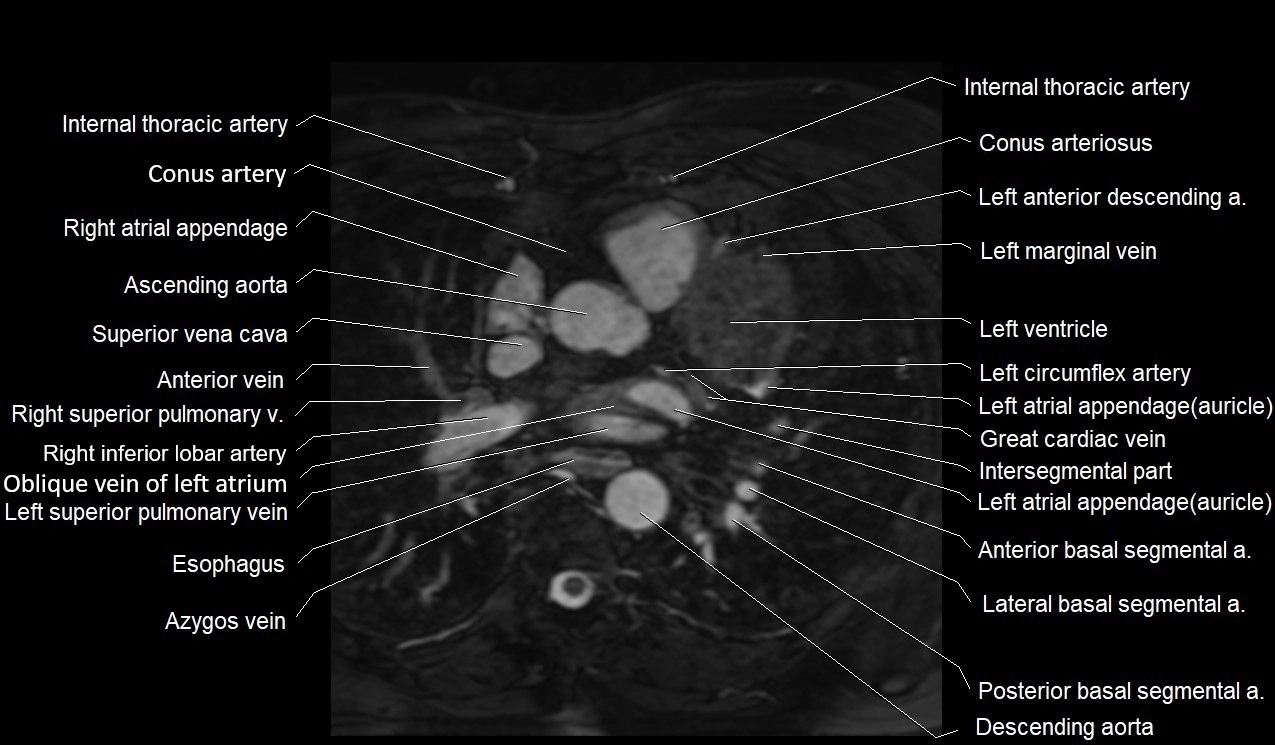

MRI image